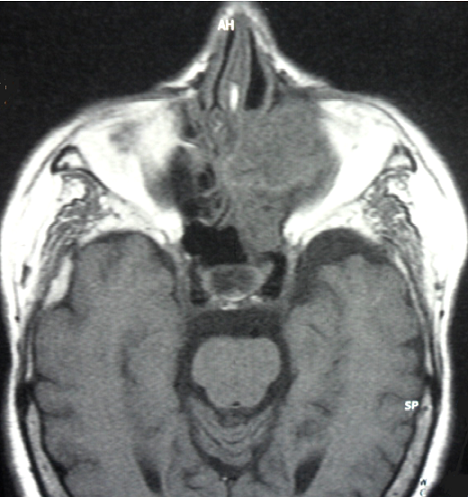

Une sinusite ethmoïdo-maxillaire chronique chez un diabétique est le plus souvent d'origine infectieuse. L'actinomycose doit être évoquée devant une forme unilatérale et trainante. Ce syndrome de sinusite chronique s'accompagne d'une tuméfaction génienne à caractère infiltrant progressif avec fistulisations multiples. Un pus contenant des grains jaunes est évocateur. La culture en milieu anaérobie confirme ce diagnostic. Patiente âgée de 73 ans, diabétique de type 2 depuis 7 ans, a consulté pour épistaxis unilatérale gauche, rhinorrhée purulente ayant un aspect de granulations jaunâtres et algies faciales. Le tout évoluait depuis un mois dans un contexte fébrile. Elle avait des caries dentaires et un diabète déséquilibré. L'endoscopie nasale a trouvé une formation charnue au niveau du méat moyen gauche avec une muqueuse nasale nécrosée. L'IRM du massif facial a révélé un comblement ethmoïdo-maxillo-nasal gauche avec lyse osseuse de la cloison inter-sinuso-nasale et des cornets et infiltration des tissus mous de l'orbite. Plusieurs diagnostics ont été évoqués en particulier une tuberculose, une aspergillose et un lymphome. La culture en milieu anaérobie a confirmé le diagnostic d'actinomycose. Le traitement chirurgical a consisté en une biméatotomie associée à une ethmoïdectomie gauche par voie endonasale, une exérèse des lésions nécrotiques et un drainage sinusien des granules. L'examen anatomopathologique a révélé une nécrose étendue de la muqueuse nasale sans aucun signe de malignité. Le traitement médical s'est basé sur la penicilline G par voie intraveineuse, l'équilibration de son diabète et le soin des caries dentaires. L'évolution était favorable avec un recul de 3 ans.